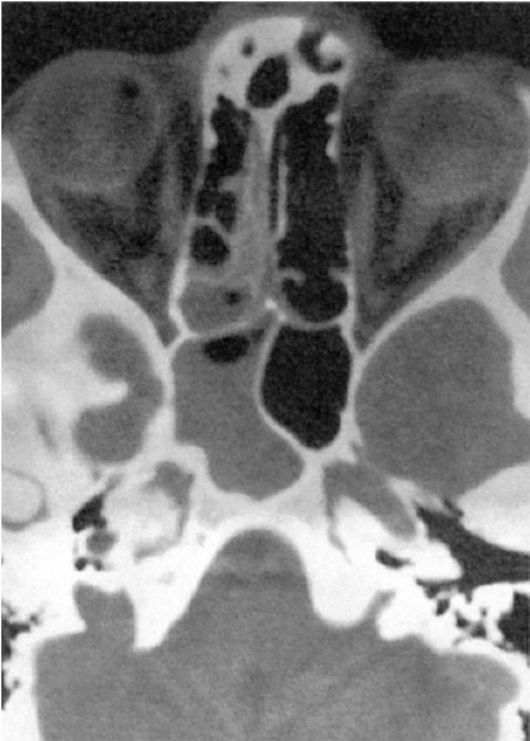

КТ-снимки хронического этмоидита: подробная визуализация

Раздел: Фотодневник открытий